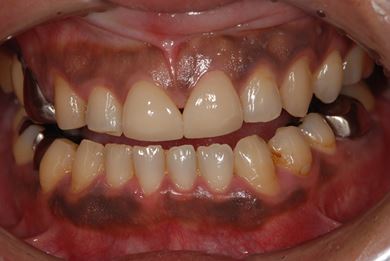

性別/年齢 男性 / 39歳

主訴 前歯のすき間を治したい。

治療方針 上顎前歯をオールセラミッククラウンにて審美的回復を行う。

治療内容 CAD/CAMオールセラミッククラウン2本

治療前

• 治療前